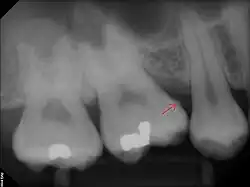

Subgingival calculus forms below the gumline and is typically darkened in color by the presence of black-pigmented bacteria,[18] whose cells are coated in a layer of iron obtained from heme during gingival bleeding.[19] The reason fossilized bacteria are initially attracted to one part of the subgingival tooth surface over another is not fully understood. However, once the first layer is attached, more calculus components are naturally attracted to the same places due to electrical charge. This is because the calcium phosphate salts contained in them exist as electrically unstable ions (unlike calcium phosphate, the primary component of teeth). The fossilized bacteria pile up rather haphazardly, while free-floating ionic components (calcium phosphate salts) fill in the gaps.[15]